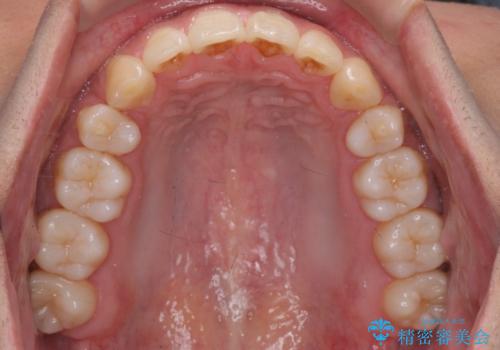

出っ歯の治療 インビザラインで抜歯矯正 親知らずを使用した矯正

- 出っ歯を主訴に来院。

上の小臼歯を2本抜歯しています。

そのかわり、上の親知らずを生かしており、歯の本数は減っていません。

矯正用ミニスクリューを使用しています(インプラント矯正)。

奥歯の歯ならびのずれが大きく、親知らずを抜いてすべて後ろに下げるか、手前の歯を抜いて前歯を下げるかの2択でした。

時間はかかりましたがしっかり前歯を下げて治療しています。